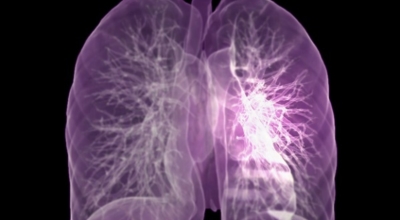

폐암이란

폐암은 폐에 생긴 악성 종양입니다. 폐 자체에 나타나는 원발성 폐암과 다른 장기에서 전이되어 온 전이성 폐암이 있습니다. 전 세계적으로 해마다 130만 명이나 되는 사람들이 폐암으로 사망하는데 이는 암에 의하여 사망하는 것 중에 가장 높은 비중을 차지하고 있습니다.